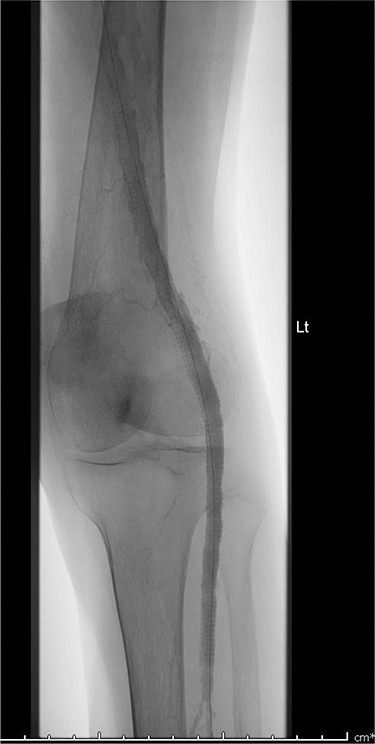

A 92-year-old female, independent from home, presented after multiple falls due to a four-month history of left foot drop. The foot drop had gradually worsened to the point that there was complete paralysis of ankle dorsiflexion and was associated with significant oedema of the foot. On examination, there was a large pulsatile mass in the popliteal fossa bilaterally. All peripheral pulses were palpable without any signs of ischemia. The most striking examination finding was complete paralysis of left ankle dorsiflexion with 0 out of 5 power. Ultrasound revealed that there were (Fig 1) bilateral popliteal artery aneurysms, which was larger on the left, causing displacement and impingement of the common peroneal nerve at the knee crease (Fig 2). Further computed tomography angiogram demonstrated an unruptured left PAA measuring 22 × 21 mm in maximal dimension over a distance of 24 mm (Fig 3). Intraluminal thrombus was also noted with 60% luminal stenosis. Distally, the arteries were heavily calcified with two-vessel runoff at the ankle. An emergency endovascular repair of the left PAA was performed by using 8 mm × 15 cm and 7 mm × 10 cm Gore Viabahn stents (Fig 4). The stents were deployed after a balloon-angioplasty and adequate decompression of the aneurysm was achieved. The postoperative period was uneventful, and patient’s pre-existing aspirin was continued. The leg and foot oedema improved rapidly over the subsequent few days. At follow-up in 12 weeks, the patient showed some return of motor function of the ankle and was walking with ankle splint. Her left leg remained well perfused with palpable pulses.

Digital subtraction angiogram image of the endovascular repair of left popliteal artery aneurysm with 8 mm × 15 cm and 7 mm × 10 cm Gore Viabahn stents.